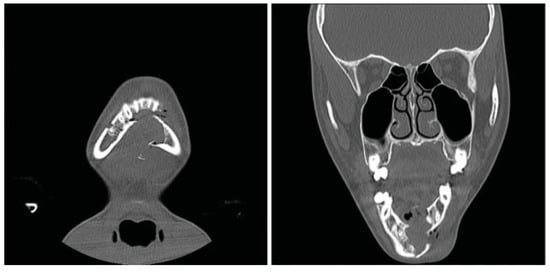

The patient was taken to the operating room the next day. With evidence of a lesion in the mandible of unknown pathology, the decision was made to proceed with a trans- cervical approach to provide broader access that would allow for adequate curettage and resection if needed. The fracture line and cystic cavity were identified. A cystic lumen was filled with organized blood clotlike material. No definitive solid tissue was identified (Figure 2). The clot and the cortex of the cavity were curetted and sent for histologic interpreta- tion. Occlusion had been established previously with max-illomandibular fixation. The mandibular fracture was reduced and repaired with a lower-border Synthes Matrix mandibular locking bar with bicortical screws (Synthes CMF, West Chester, PA, USA). An additional 2.0 Synthes Matrix mono- cortical plate was used to secure a sizable secondary fragment of the cystic wall (Figure 3). The cystic space was packed with Gelfoam (Pfizer, Pharmacia and Upjohn Company, Kalamazoo, MI, USA), as a means of filling the cystic dead space with a nonpermanent material that would not interfere with later osteogenesis. The remainder of surgery was uncomplicated and a small suction drain was placed at closing. A postoperative image revealed satisfactory alignment (Figure 4). The drain was removed on postoperative day 2, and the patient was dis-charged home 3 days later, tolerating a soft diet. Fifteen days after discharge, the patient returned to our ED with worsening pain and swelling at the surgical site. He was diagnosed with a small submental abscess. The patient was admitted and treated successfully with bedside incision and drainage and a short course of intravenous antibiotics. The remainder of his recovery was uneventful, with good occlusion and function. Follow-up CT imaging at 6 weeks showed good fracture healing and some early osteogenesis within the cystic cavity (Figure 5). One year after surgery, he had normal occlusion and no evidence of hardware complications. Additionally, CT imaging demonstrated ossification of the majority of the cystic space, with only a few small lateral areas of persistent cyst (Figure 6).

Figure 6.

Panorex computed tomography scan obtained 1 year postoperatively demonstrating near-complete ossification of the cys- tic defect of the mandible.